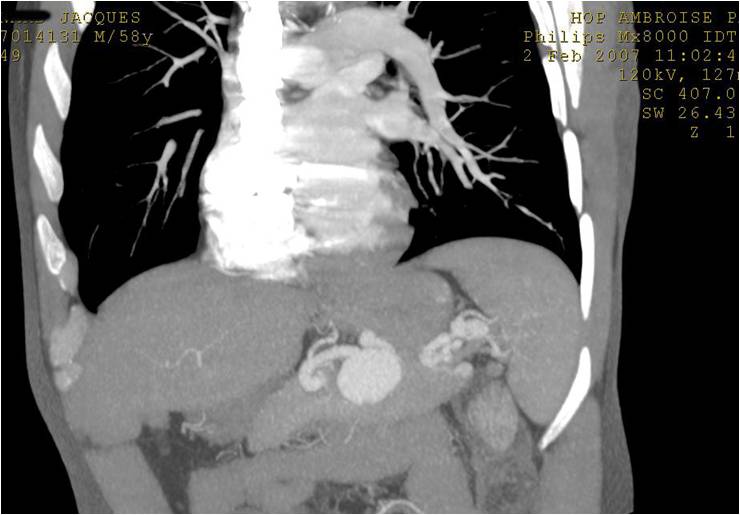

肺动静脉畸形的栓塞

|

肺动静脉畸形CT |

肺动静脉畸形血管造影(动脉显影) |

肺动静脉畸形血管造影(静脉显影) |

肺动脉栓塞后 |